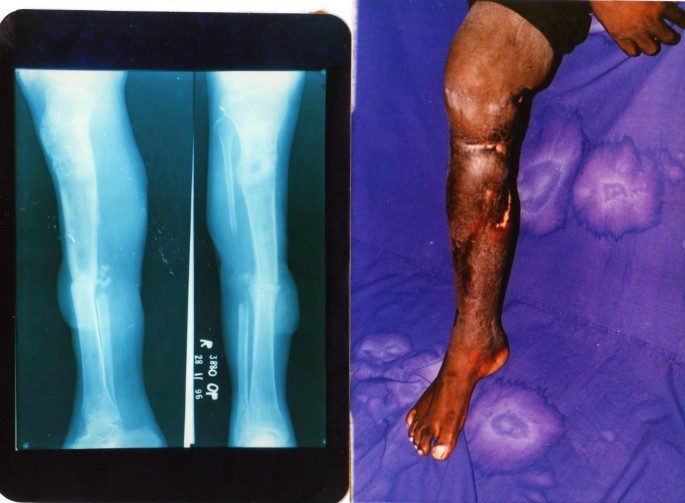

The demographic details of patients are as per additional file 1. The study group consisted of 22 patients in the age group of 20 – 52 years [Average: 37.2]. There were 18 male and 4 female patients. All patients had limb oedema, equinus deformity of the ankle [12–23 degrees, Average: 15.7 degrees], ankle, and sub-talar and knee joint stiffness [figures 1a, 2a, 2b, 3a, 3b, 4a, 4b, 4c, 5a, 5b]. Fracture union was achieved in 18 patients without the need for bone grafting. The problems and complications in the cohort of patients studied are as per Table 1.

In 1 patient, there was re- fracture and refused a re-application of the fixator. 3 patients discarded the fixator while on treatment. There were 167 episodes of pin-tract infection in all and 2 patients had abscess, cellulitis and septic arthritis of the knee, which required arthrotomy and drainage, change of wires and repositioning of the rings. Wire breakage was seen in 7 patients. Persistent bone infection despite bony union was evident in 6 patients. 4 patients had residual shortening of 3 cms and treatment was discontinued on patient's request after bone union was confirmed. There was limb oedema in all patients despite fracture union. Healing of sinuses and open wounds was satisfactory without the need for additional plastic surgical procedures. Knee, ankle and sub-talar joint stiffness persisted in all and worsened in 7 patients. Deformity correction in the sagittal plane was less satisfactory compared to the correction in the coronal plane. Bony and functional results [Tables 2 and 3] were evaluated as laid down by the ASAMI Criteria.